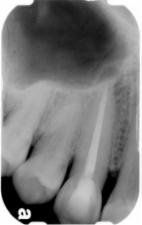

Apexification

In this case, the unhealthy pulp is removed. The MTA will be placed into the apical portion of the root to stimulate hard tissue to form near the root tip (approximately 4-5 mm's of MTA condensed carefully into the apical portion of the root). The coronal portion of the canal space is then filled with restorations to re-enforce the root and provide more structural integrity. The patient is recalled periodically to monitor the progress of the root-end closure, and decide whether other measures, like root end surgery, may be required.